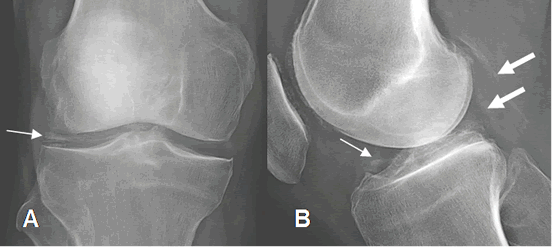

Fig 195. Artropatía por cristales.

A: Rx AP. Calcificación del menisco externo.

B:

Rx AP. Calcificación meniscal (Flecha delgada) y de la cápsula articular. (Flechas gruesas).